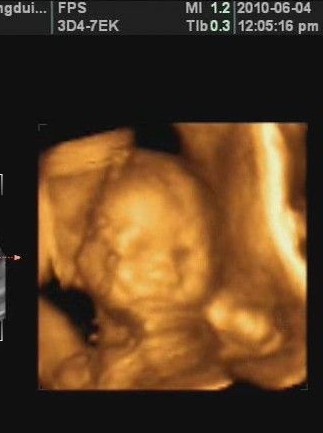

怀孕22周是第五个月了哦,此时的宝宝在妈妈肚子里的大小我们可以从四维彩超图中查看到,他现在有19厘米长,350克了。现在,血液正在以每小时约6.5千米的速度穿过脐带,用氧和营养物质支持他的成长。宝宝的脑部开始迅速生长,尤其是位于大脑中心的生发基质,它负责产生脑细胞。

这时的胎儿已经可以听到你的声音,如果你为他(她)讲故事、唱歌、播放音乐或者跟他(她)聊天,他(她)都能听得见。胎宝宝现在看起来像一个“小人儿”了,只是脸上皱巴巴、红红的,头上、脸上布满了胎毛。眉毛和眼睑已清晰可辨,小手指已长出娇嫩指甲。